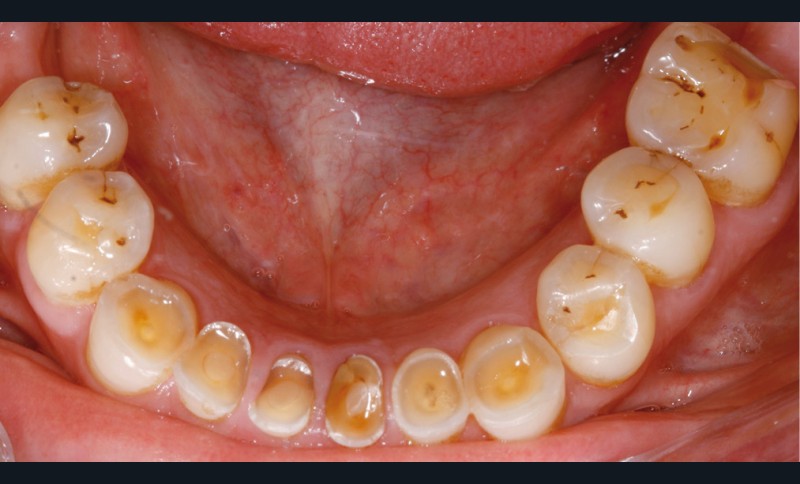

• L’examen intrabuccal montre de nombreux édentements non compensés (14, 15, 16, 24, 25, 26, 27, 47 et 36) ainsi que des pertes de substance très importantes, notamment dans le secteur antérieur.

Une attrition sévère, couplée à une occlusion sans calage postérieur, a engendré des difficultés pour s’alimenter.

La perte de dimension verticale par usure prématurée nécessite d’augmenter cette dernière de façon importante, et en une seule fois.

– égressions compensatoires.